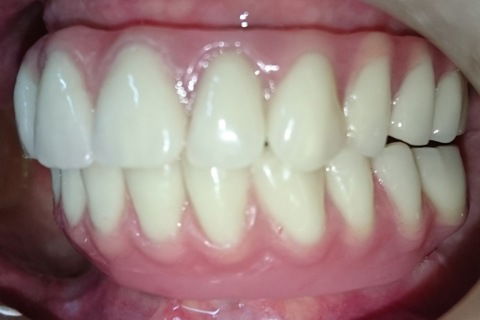

Aspecto final de frente